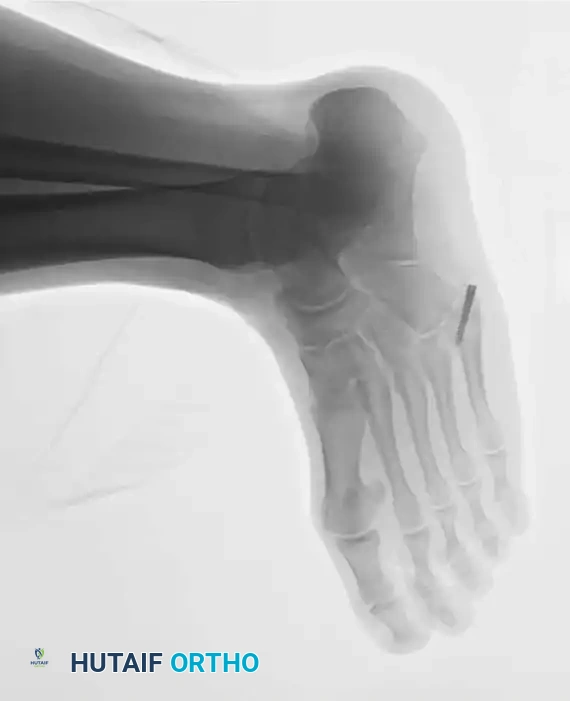

Fig. 86-45 A-C. Type IA (DeLee) fifth metatarsal fracture in a collegiate soccer player, representing an ideal candidate for early intramedullary fixation.

Fig. 86-45 A-C, Type IA (DeLee) fi fth metatarsal fracture in collegiate soccer player. D-F, After fi xation with variable pitch compression screw.

Fig. 86-45 D-F. Postoperative imaging after robust fixation utilizing a variable pitch compression screw, ensuring excellent compression across the fracture site.